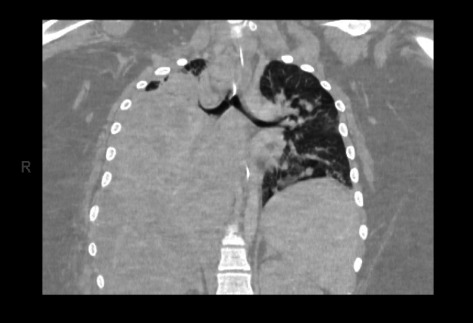

芽生菌病是一种罕见的真菌感染,由吸入皮炎芽生菌孢子引起。这种真菌感染几乎可以影响每个器官系统,尽管肺部疾病是最常见的。肺芽孢菌病的表现变化很大,从临床无症状到需要重症监护的严重呼吸衰竭。本病例系列描述了两个兄弟姐妹的临床表现、诊断挑战、管理和结果,他们患有严重的肺芽孢菌病,并发展为儿童急性呼吸窘迫综合征,需要机械通气和静脉-静脉体外膜氧合(VV-ECMO)。尽管相对罕见,但在呼吸道症状对经验性抗菌治疗无反应的患者中,应考虑芽生菌病,特别是在流行地区。早期诊断和及时开始适当的抗真菌治疗对良好的结果至关重要。此外,对于严重的肺芽孢菌病,早期开始ECMO可能有利于延缓时间,以便有足够的时间对抗真菌治疗产生充分的反应。

Blastomycosis is a rare fungal infection caused by the inhalation of Blastomyces dermatitidis spores. Infection with this fungus can impact nearly every organ system, though pulmonary disease is the most common. Presentations of pulmonary blastomycosis are highly variable, ranging from clinically asymptomatic to severe respiratory failure requiring intensive care. This case series describes the clinical presentation, diagnostic challenges, management, and outcomes of two siblings with severe pulmonary blastomycosis that progressed to pediatric acute respiratory distress syndrome requiring mechanical ventilation and venovenous extracorporeal membrane oxygenation (VV-ECMO). Despite being relatively uncommon, blastomycosis should be considered in patients with respiratory symptoms not responding to empiric antibacterial therapy, particularly in endemic regions. Early diagnosis and prompt initiation of appropriate antifungal therapy are crucial for favorable outcomes. Additionally, early initiation of ECMO for severe pulmonary blastomycosis may be beneficial in temporizing to allow time for sufficient response to antifungal therapy.